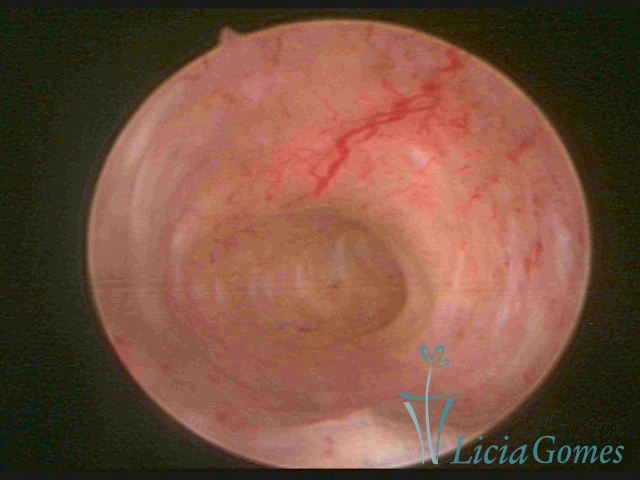

Unicornuate uterus

It presents a tubular cavity with an impaired intracavitary space, resembling the shape of a banana, whose the narrowest edge contains the tubal ostium. The endometrium is compatible with the menstrual cycle and the cervical canal is normal, in structure and trophism.